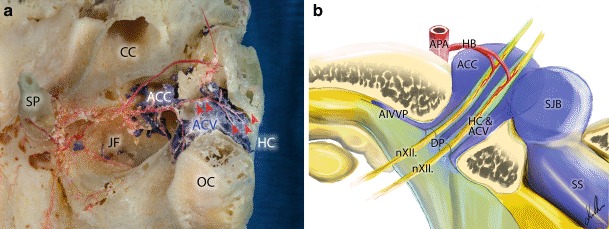

Fig. 4.

Anatomical relations within and around the hypoglossal canal on the right side. a Macerated bony specimen of the hypoglossal canal. Note the hypoglossal branches of the ascending pharyngeal artery within the hypoglossal canal (red arrowheads). b The two presented trunks of the hypoglossal nerve enter the hypoglossal canal through separate dural pores. The trunks have their own separate dural sheaths within the canal surrounded by a dural venous sinus called the anterior condylar vein. Each trunk has its own arterial blood supply through the hypoglossal artery originating from the neuromeningeal branch of the ascending pharyngeal artery. The anterior condylar vein drains into the anterior condylar confluence located at the extracranial opening of the hypoglossal canal. This venous pouch is connected to the superior bulb of the internal jugular vein. ACC anterior condylar confluence, ACV anterior condylar vein, AIVVP toward the anterior internal vertebral venous plexus, APA anterior pharyngeal artery, CC carotid canal, DP dural pores, HB hypoglossal branch, HC hypoglossal canal, JF jugular fossa, nXII hypoglossal nerve, OC occipital condyle, SJB superior bulb of the internal jugular vein, SP styloid process, SS sigmoid sinus

The arterial supply of this region is provided by the ascending pharyngeal artery (APA). The neuromeningeal branch of the APA runs parallel to the internal jugular vein towards the jugular foramen, where it bifurcates. One of the branches enters the jugular foramen and supplies the dura of the posterior fossa. The other branches enter the HC and supply the neuromeningeal structures located within the canal. The hypoglossal nerve can sometimes enter the HC via two or more dural pores. In such cases the individual trunks have their own dural sheaths along the entire length of the canal. The arterial blood supply of these individual trunks is provided by their own branches from the neuromeningeal trunk of the APA through the hypoglossal canal (Fig. 4a, b). This variation was observed in nearly half of the cadaveric samples (17 out of 40).

The arterial supply of the examined region is well-described in literature [17]; however, we found an interesting, previously undescribed anatomical variation of the arteries within the HC: in some cases the hypoglossal nerve is divided by dural sheaths to numerous trunks within the HC and these trunks have each their own arterial supply from the APA (Fig. 4a, b). Although there are reported cases of IX–XII cranial nerve dysfunctions after transarterial embolization of DAVFs in the region of the ACV [18], this anatomical fact is a possible explanation why hypoglossal nerve injury is not a frequently observed therapeutic injury.